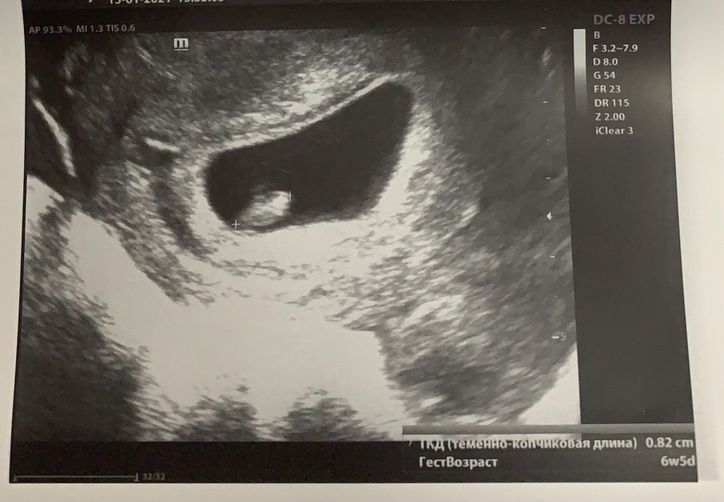

УЗИ 31 ДПП

Я БЕРЕМЕННА !Девочки, всем привет. Сходила я на УЗИ:

ПЯ 33*15*36 мм

ЖМ 3мм

КТР 8,2 мм

СБ129 уд/мин

Как я понимаю здесь все хорошо? ☺️

Но есть одно но, ПЯ расположенно в средней и нижней трети полости матки и сказали, что это рассматривается как угроза. Девочки, у кого так же было? Как проходила беременность 🤰?